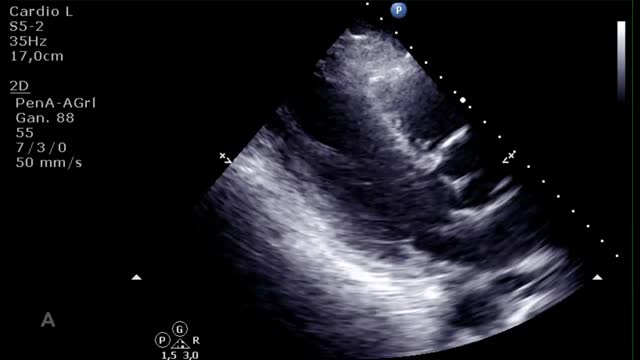

El aumento de la poscarga que condiciona la ECMO, junto con la baja contractilidad ventricular izquierda, puede comprometer la apertura valvular aórtica, pudiendo presentar un cierre precoz de la válvula (suplementario 13) e incluso permanecer cerrada (fig. 3 y suplementario 14).

El cierre aórtico es una complicación indeseada y que se debe resolver ya que, si se perpetúa, condiciona una estasis sanguínea a nivel intraventricular y un aumento de las presiones izquierdas que se traduce en una dilatación de cavidades izquierdas y, finalmente, en edema pulmonar persistente. En caso de que esto ocurra, en la ETT podremos ver humo o incluso trombos intraventriculares y signos de altas presiones (una relación E/A>2 y/o un tiempo de desaceleración del flujo mitral<150ms) izquierdas. Además de la utilidad diagnóstica/evolutiva, la ETT nos ayudará a guiar el tratamiento de esta complicación mediante la evaluación de la rentabilidad del uso/aumento del tratamiento inotrópico (suplementario 21) o guiando la implantación de dispositivos (BCIAo/Impella®) o intervencionismos (septostomía auricular, drenaje apical, ECMO veno-arterial de aurícula izquierda) para la descarga de presiones izquierdas12.

Evaluación ecocardiográfica de destete de paciente con ECMO VA. Ecografía transtorácica e integral velocidad-tiempo (IVT) del tracto de salida del ventrículo izquierdo al reducir flujo (A: 3L/min, B: 2,5L/min, C: 2L/min) de ECMO VA. Obsérvese el aumento del tamaño de la IVT y consecuentemente del volumen sistólico y del gasto cardiaco.